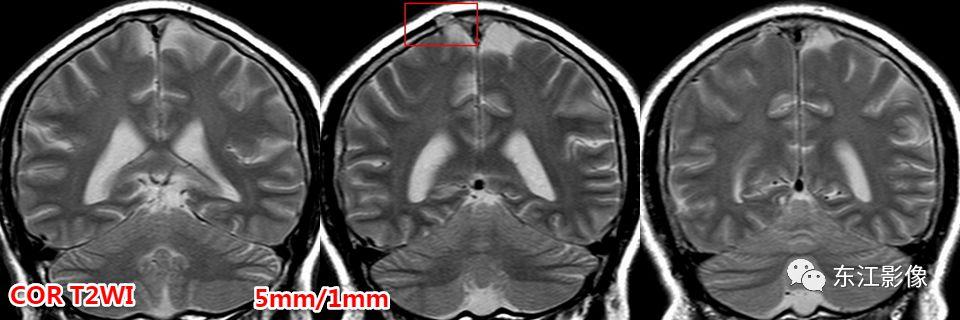

5. 脑脊液流动伪影

- 脑脊液流动伪影主要见于T2WI、FLAIR,主要是长TE序列容易出现流空效应的缘故。

- 但由于脑脊液流动方向、速率不一等因素的影响,呈现为非脑脊液信号影像,部分呈囊样。

- 常见于第三脑室、侧脑室室间孔旁区、脑干周围脑池(这些区域结构复杂)。

- 鉴别要点,T1WI、增强未能辨认;DWI与邻近一致的无信号;无占位效应。

桥前池脑脊液流动伪影。